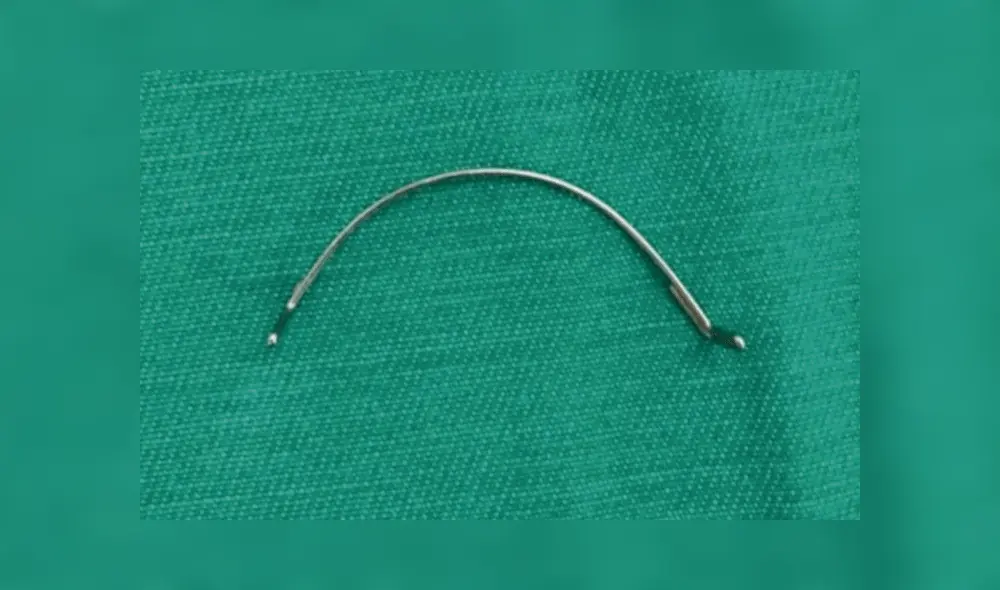

La menor fue sometida al proceso quirúrgico y la operación salió exitosa. Actualmente, se recupera favorablemente en el Instituto Nacional de Enfermedades Respiratorias y del Ambiente Juan Max Bohener (Ineram) luego de ser sometida al procedimiento el pasado lunes por la mañana.

Una joven de 15 años sufrió un terrible accidente: mientras almorzaba en su vivienda de Paraguay, se tragó el expansor de paladar que usaba para su tratamiento de ortodoncia.

El sábado por la tarde A. M se encontraba comiendo junto a su familia en la sala de su casa, cuando de pronto, en el segundo bocado sintió que ingirió algo extraño por lo que comenzó a revisar su dentadura y se dio cuenta de que el expansor de los brackets no estaba en su lugar.